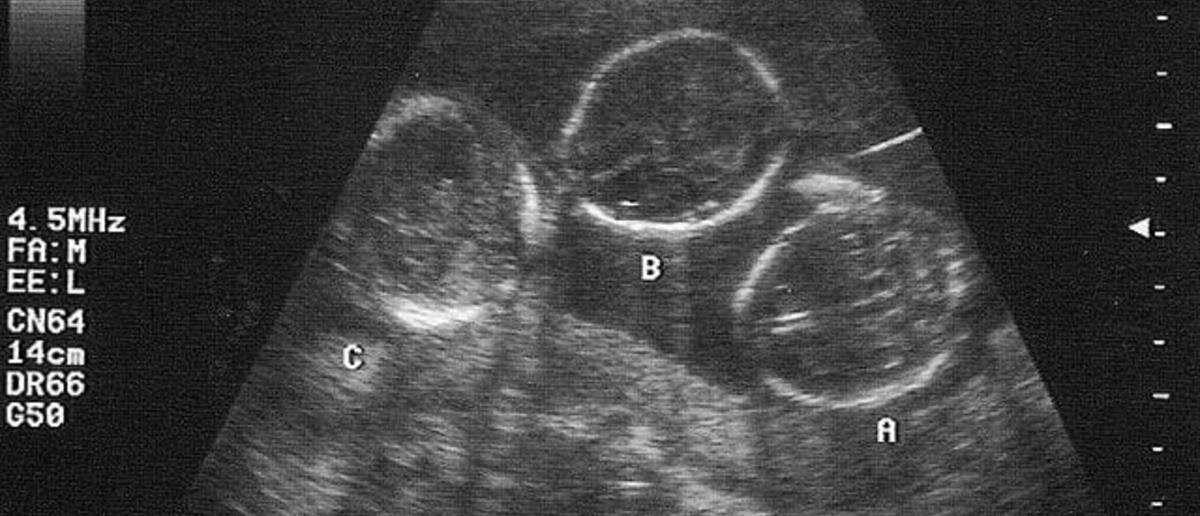

Πιο συγκεκριμένα, τρίδυμα γεννήθηκαν για πρώτη φορά στη χώρα μας προερχόμενα απο τον ίδιο πλακούντα, ανέφερε στην εκπομπή Περίμετρος της ΕΡΤ3.

Μάλιστα, σύμφωνα με τον γυναικολόγο, Νίκο Παπανικολάου, πρόκειται για τρίδυμα κοριτσάκια που προέρχονται από τον ίδιο πλακούντα, μονοζυγωτικά, φαινόμενο πολύ σπάνιο στην ιατρική βιβλιογραφία, καθώς όπως επισήμανε επίδή τρέφονται από τον ίδιο πλακούντα, υπάρχει η περίπτωση κάποιο από τα τρία να μην αναπτυχθεί σωστά και να συμπαρασύρει τα άλλα δύο.

Τα τρίδυμαμάλιστα, προέκυψαν μάλιστα από αυτόματη σύλληψη. Η συχνοτητα εμφανισης τετοιας περιπτωσης στην ιατρικη ειναι μικροτερη του 1: 100.000 και στην ελληνική βιβλιογραφία δεν έχει εμφανιστεί αντίστοιχο τέτοιο περιστατικό.